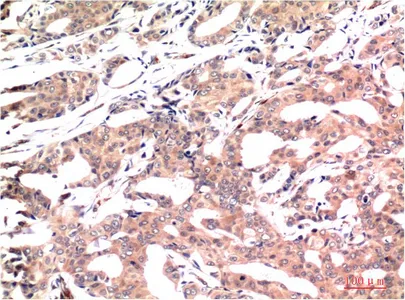

Galectin 3 (7G9) Mouse Monoclonal Antibody

Cat: AMM03624

Size1:50μl Price1:$150

Size2:100μl Price2:$280

Size3:500μl Price3:$1200

Size2:100μl Price2:$280

Size3:500μl Price3:$1200